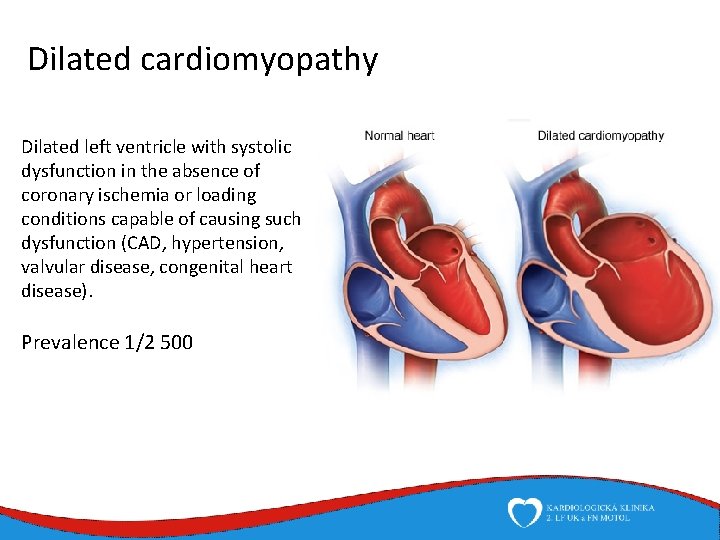

Dilated cardiomyopathy Dilated left ventricle with systolic dysfunction in the absence of coronary ischemia or loading conditions capable of causing such dysfunction (CAD, hypertension, valvular disease, congenital heart disease). Prevalence 1/2 500